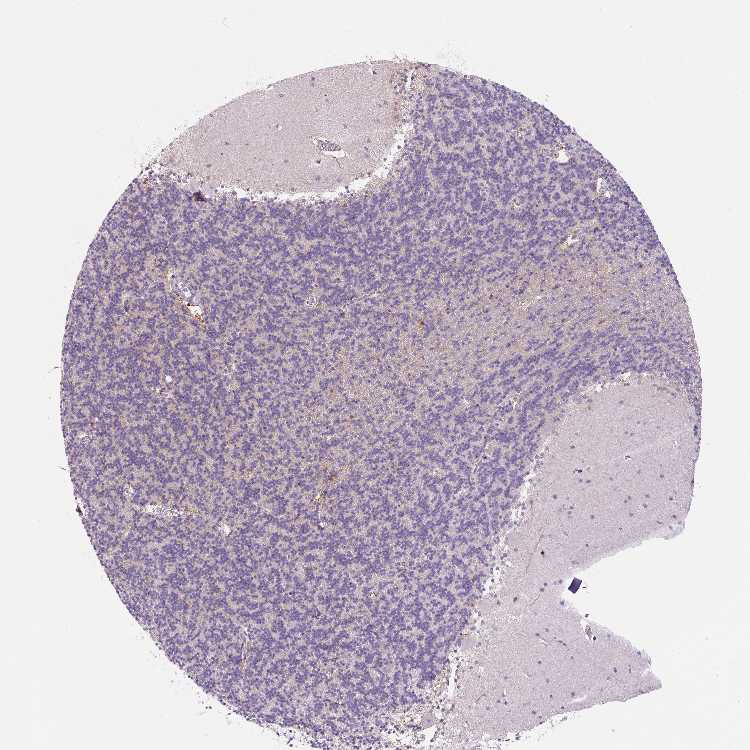

CEREBELLUM - Antibody stainingi

Antibody staining in the annotated cell types in the current human tissue is reported as not detected, low, medium, or high, based on conventional immunohistochemistry profiling in selected tissues. This score is based on the combination of the staining intensity and fraction of stained cells.

Each image is clickable and will lead to virtual microscopy that enables deeper exploration of all samples and also displays staining intensity scores, fraction scores and subcellular localization as well as patient and tissue information for each sample.

Antibody HPA053357

Purkinje cells Not detected

Cells in granular layer Not detected

Cells in molecular layer Not detected